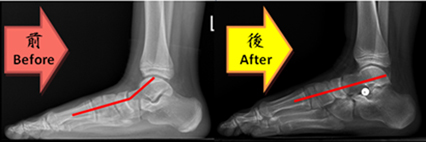

如有前述症狀,且使用保守治療後仍無效者,建議手術矯正治療。仍在成長期的兒童(一般為國小階段)可接受踞骨下矯正器置入(又稱距下關節制動術subtalar arthroeresis) 手術合併跟腱延長、後脛肌加強術,(圖二、三),筆者建議此類手術最佳的年齡為7-12歲之兒童,此時兒童筋骨較為柔軟,手術後恢復期較短,矯正效果也較好。

圖三、手術治療前與手術治療後,距骨與第一蹠骨夾角於術後獲得改善(28度→0度)